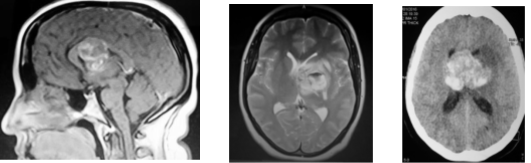

Se realizó una tomografía computada postoperatoria inmediata (Figura 3) que mostró la resección total de la lesión, además se observó una restauración casi completa de la morfología del sistema ventricular.

Figura 3: Tomografía axial computada de encéfalo postoperatoria.